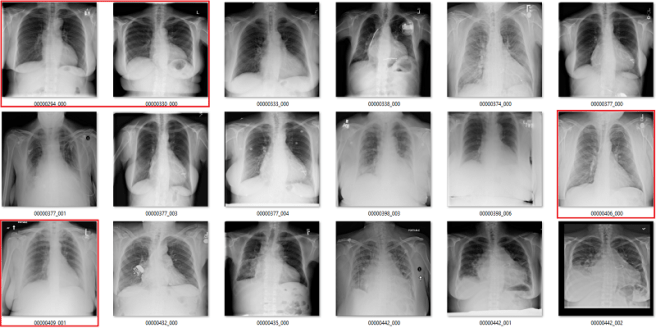

Complete nonsense as far as I can tell. Below are the model predictions, compared against the labels in the dataset. Again, the same technique as earlier for picking images. I’m confident these aren’t cherry picked.

True positives

The green ones are the only actual true positives. The rest have incorrect labels.

True negatives

There are one or two arguable ones in the top 18, but I gave the labels the benefit of the doubt. The red ones in the 2nd 18 are all wrong.

False positives

The red ones are wrong. It also turns out that there are rotated, inverted, distorted, and otherwise abnormal images in the dataset (shown by the red question mark). More on that in the next post.

False negatives

Again, the red ones are wrongly labelled.

Despite an apparent AUC of 0.7 we get really bad classification performance, in line with the label inaccuracy. The model didn’t just ignore the incorrect labels and produce sensible predictions. It was not robust to label noise. Most importantly, the AUC value does not reflect the clinical performance.

This is a huge problem.

This AI system learned to reliably produce meaningless predictions. It managed to learn image features that create the above groups of “opacity” cases with almost no airspace opacities, and “no opacity” cases with big groups of severely abnormal lungs.